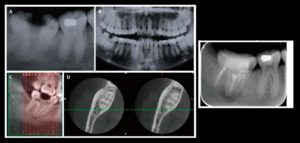

132 – Tratamiento de la reabsorción radicular interna idiopática perforante: controles radiográficos

La reabsorción radicular interna (RRI) es una afección inflamatoria que resulta en la destrucción progresiva de la dentina intra-radicular a lo largo de los tercios